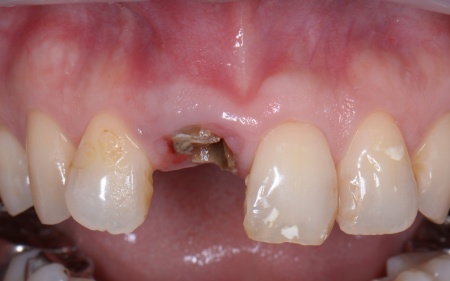

拝見したところ、左下奥歯(第1大臼歯)は以前、歯根分割処置が行われていました。

歯根分割処置とは、歯周病や虫歯などにより複数ある歯根のうちひとつだけがダメージを受けた場合に施す外科的な治療法です。

特に根が複数ある大臼歯に対して行われ、問題のある歯根のみを分割して抜くため残りの健康な歯根を残すことが可能です。

しかし残していた歯根の状態も悪化しており、治療しても温存は困難と判断しました。

さらに患者様は全体的に歯並びや噛み合わせに問題があり、特に上下の前歯は噛んだ際に隙間ができ食べ物を噛み切りにくい状態です。

左下奥歯はこのまま放置すると細菌感染を引き起こすため抜歯が必要なこと、抜歯後に歯を補うため人工歯根を利用したインプラント治療を提案し、同意いただきました。